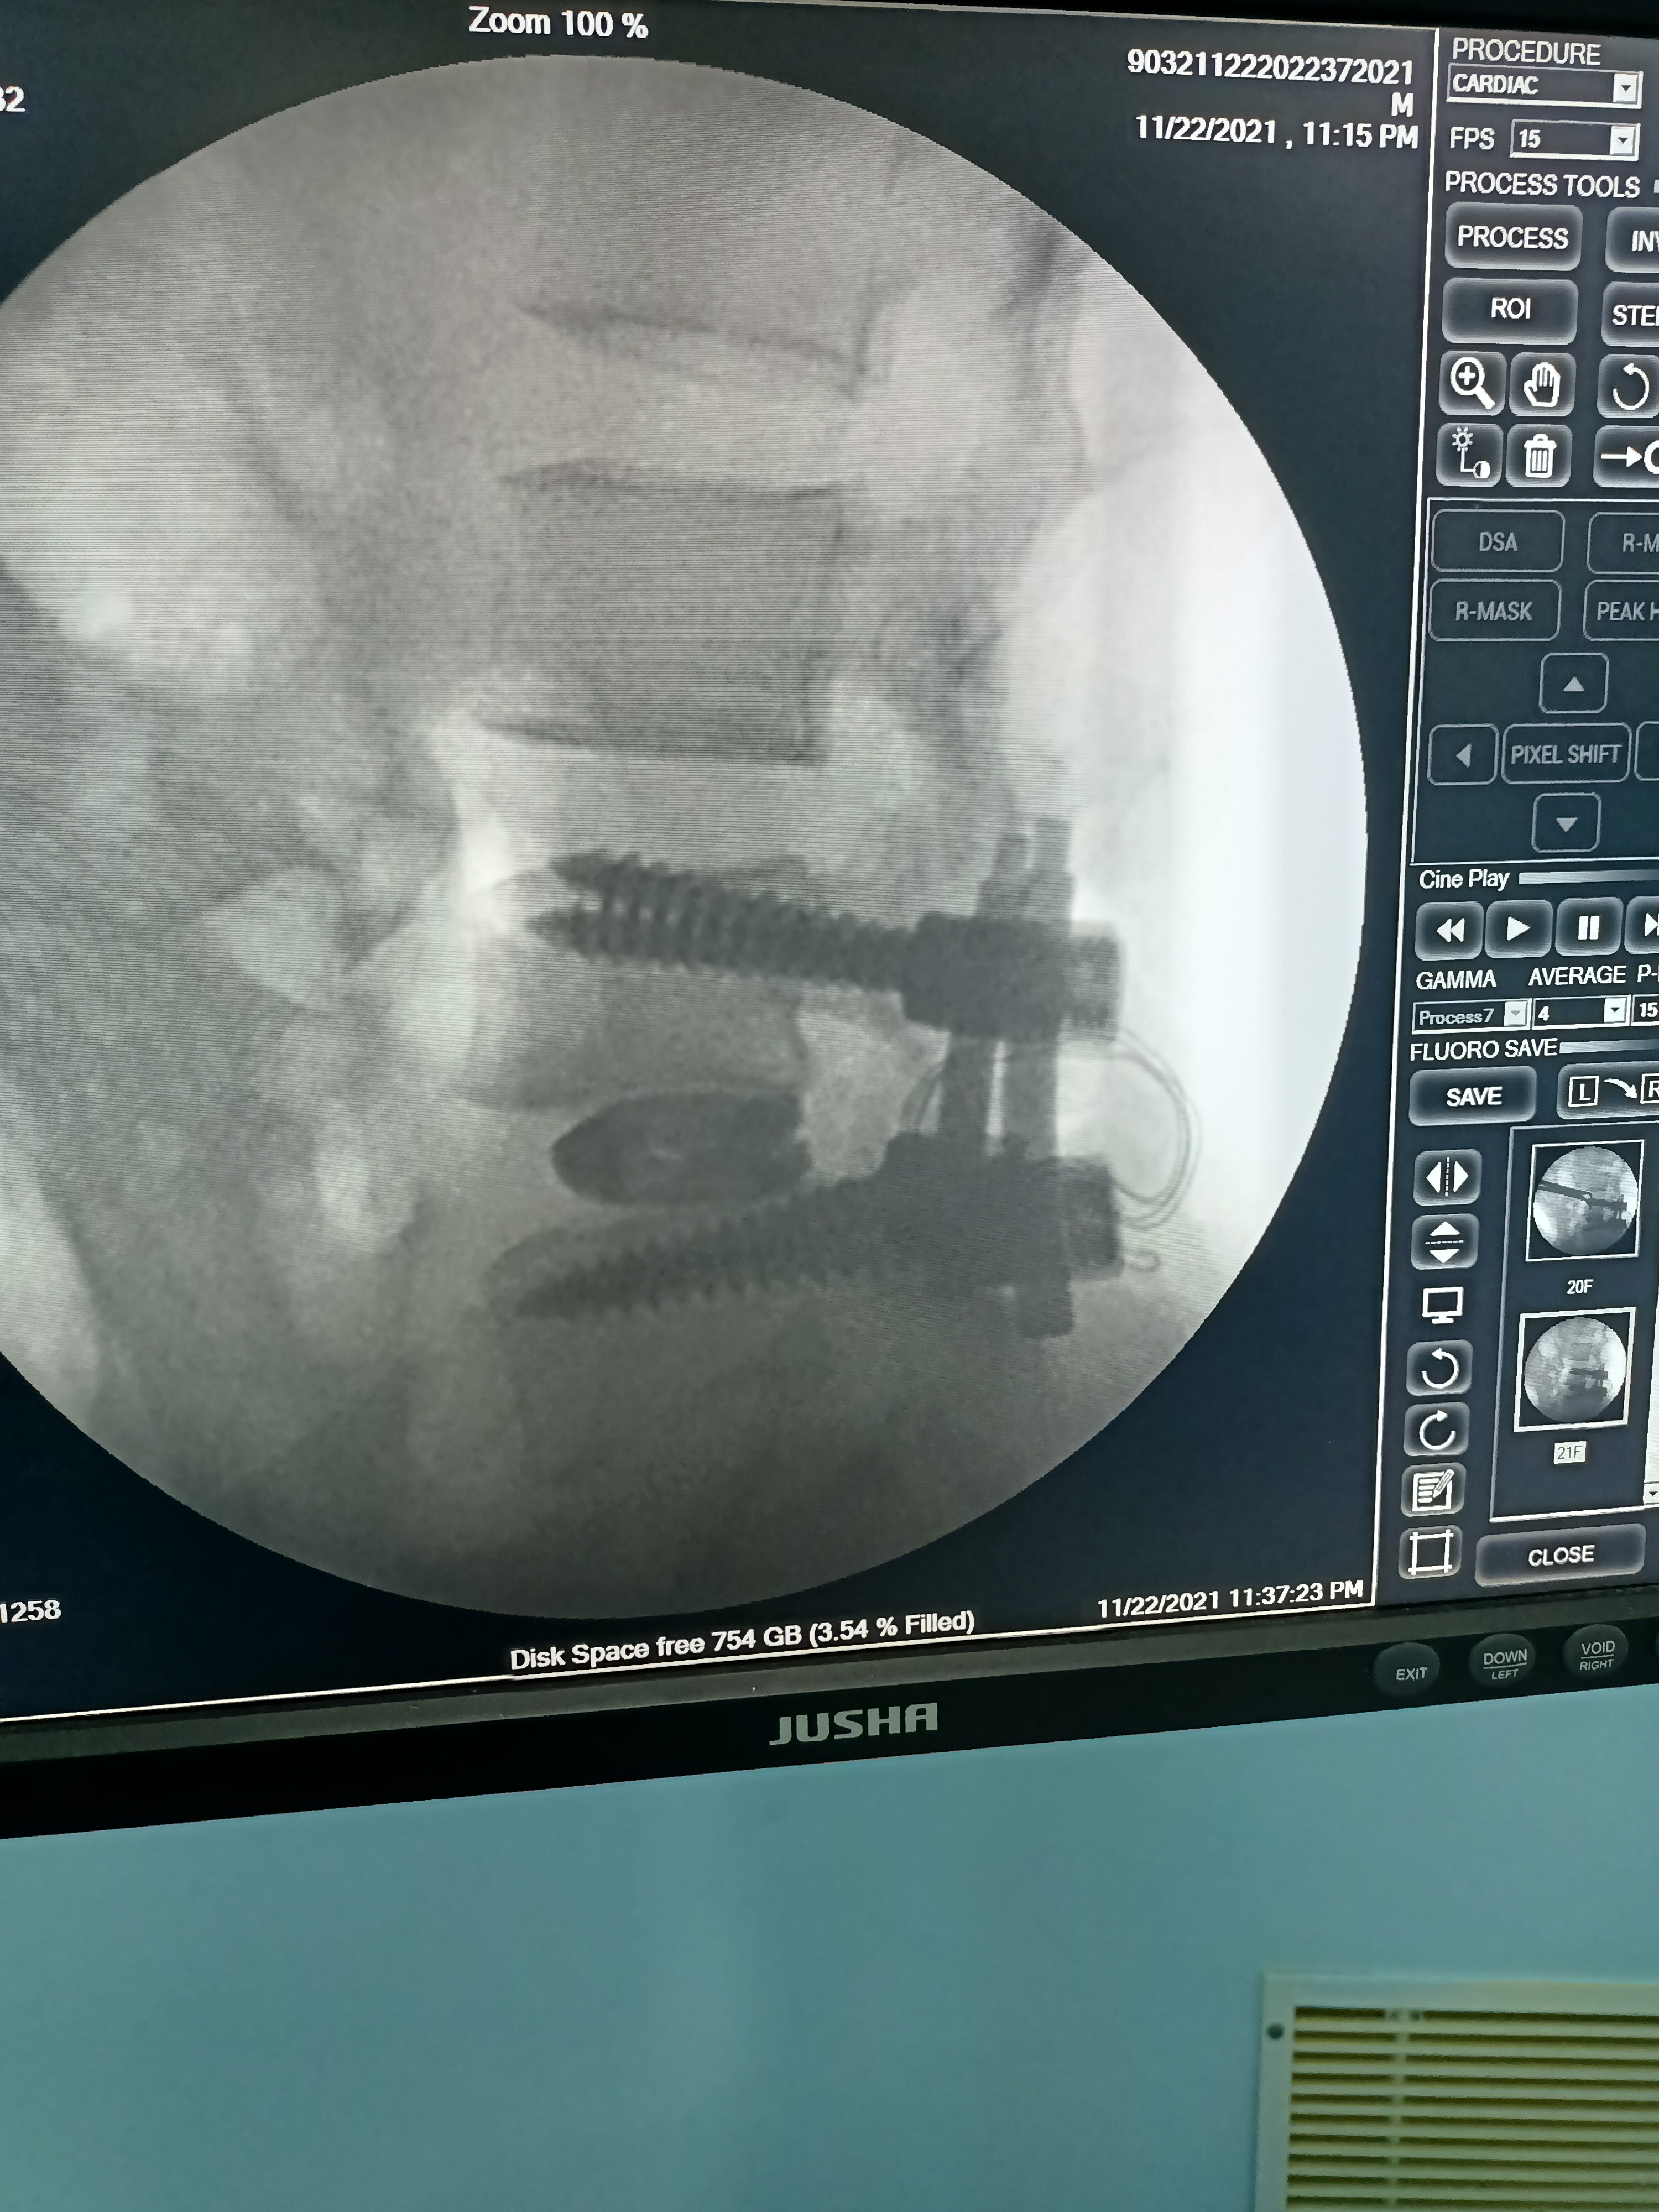

Slip disc with Sciatica TLIF- Laminectomy and Fusion